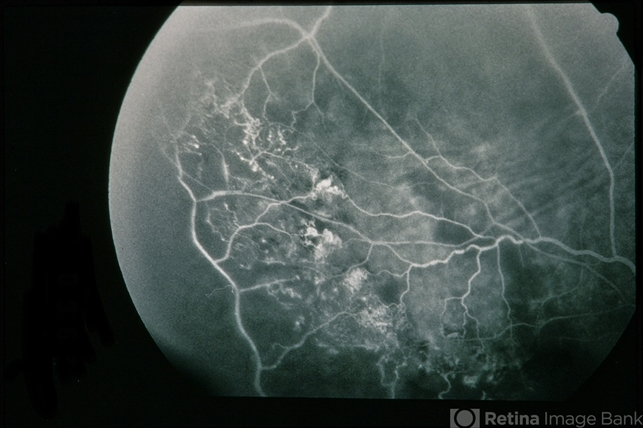

- BRVO Massive Exudate from Collaterals

- branch retinal vein occlusion (BRVO), exudate, collaterals

- 66-year-old female with BRVO - massive exudate from collaterals, 20/70 OD; 20/25 OS in 1985; +HTN, glaucoma; 20/200 OD 1987.